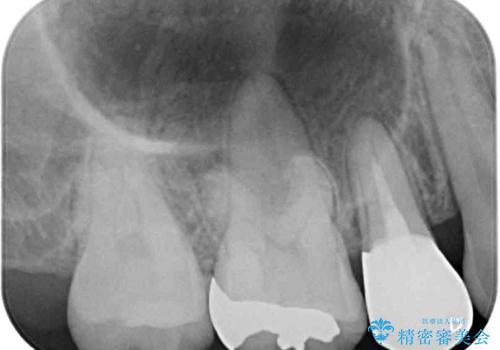

- 結婚式に向けて、八重歯と虫歯で変色した歯を改善したいとのことで来院された患者様です。

上下ともにデコボコが強いため、上下顎左右小臼歯各1歯を抜歯して歯列を整えることとしました。

大きな虫歯が認められた歯は、矯正治療後にオールセラミッククラウンにて補綴治療を行うこととしました。